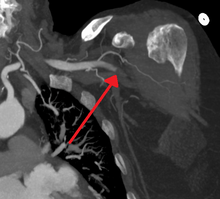

Acute embolism to the right femoral artery resulting in ischemia | |